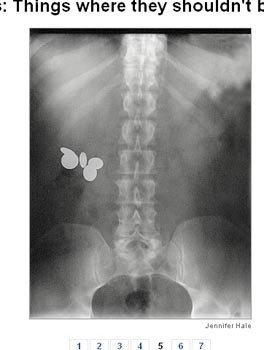

Trẻ con nhiều khi rất thíc nuốt tiền xu